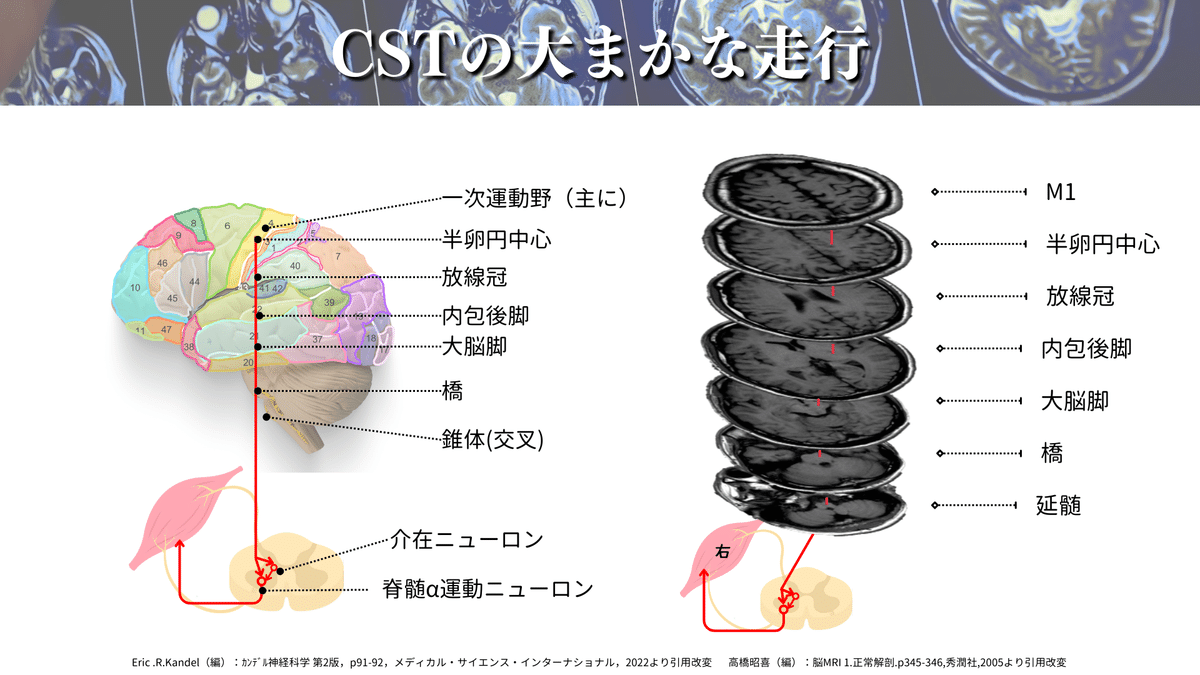

さらに詳しく見ていくと、下図のようなポイントを通過していきます🏃♀️

CSTの代表的な通過ポイント

・一次運動野(6野や3.1.2野からの出力もあります)

・半卵円中心

・放線冠

・内包後脚

・大脳脚(中脳)

・橋

・延髄(錐体交叉)

MRIで見るとこんな感じです⬇️

かなりイメージできてきたのではないでしょうか🤭?